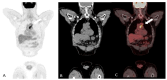

Systemic vasculitides are a rare and complex group of diseases that can affect multiple organ systems. Clinically, presentation may be vague and non-specific and as such, diagnosis and subsequent management are challenging. These entities are typically classified by the size of vessel involved, including large-vessel vasculitis (giant cell arteritis, Takayasu's arteritis, and clinically isolated aortitis), medium-vessel vasculitis (including polyarteritis nodosa and Kawasaki disease), and small-vessel vasculitis (granulomatosis with polyangiitis and eosinophilic granulomatosis with polyangiitis). There are also other systemic vasculitides that do not fit in to these categories, such as Behcet's disease, Cogan syndrome, and IgG4-related disease. Advances in medical imaging modalities have revolutionized the approach to diagnosis of these diseases. Specifically, color Doppler ultrasound, computed tomography and angiography, magnetic resonance imaging, positron emission tomography, or invasive catheterization as indicated have become fundamental in the work up of any patient with suspected systemic or localized vasculitis. This review presents the key diagnostic imaging modalities and their clinical utility in the evaluation of systemic vasculitis.